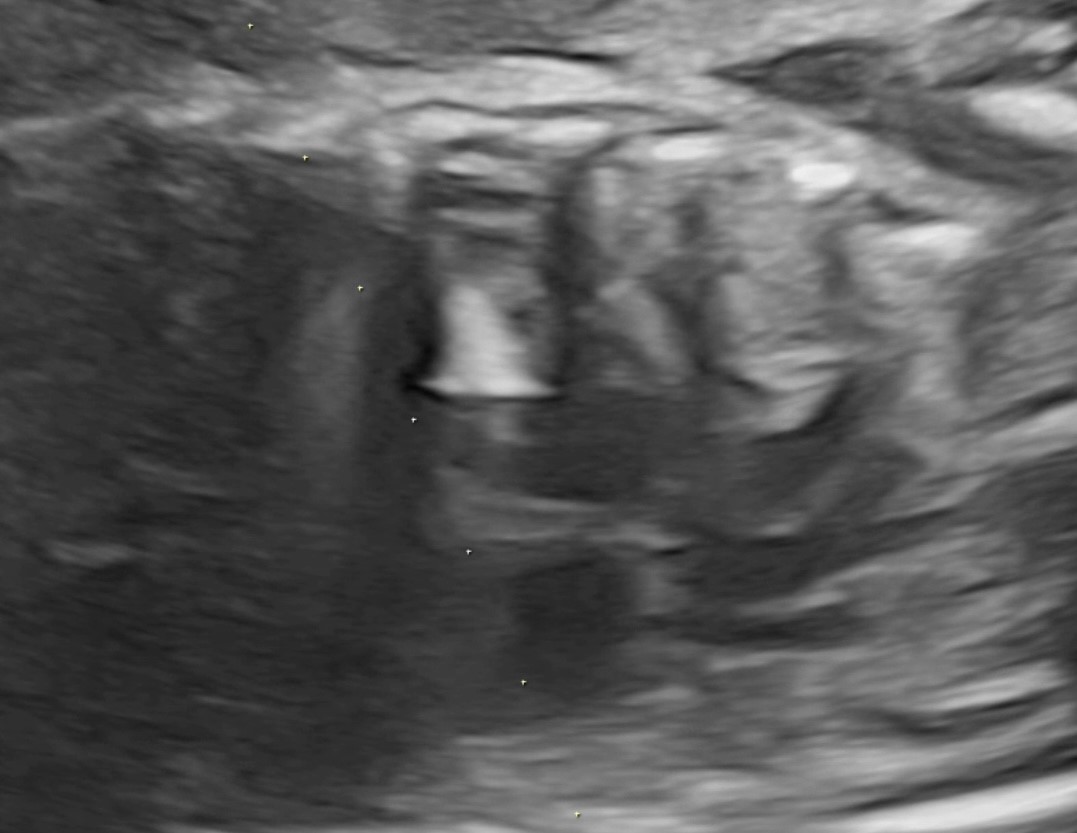

3 a. до выполненной вальвулопластики клапана аорты

3 b. после выполненной вальвулопластики клапана аорты и извлечения баллона с иглой

По данным ультразвукового исследования после выполненной вальвулопластики клапана аорты и извлечения баллона с иглой отмечается увеличение эффективного отверстия клапана аорты и отсутствие жидкости в полости перикарда.

Через 12 часов после операции было проведено ультразвуковое исследование сердца плода. Фракция выброса ЛЖ увеличилась до 24 %, диаметр эффективного отверстия АК составил 2,9 мм. Максимальный градиент на АК возрос до 21 mm Hg, митральная регургитация уменьшилась с тотальной до 2 степени. Жидкости в полости перикарда обнаружено не было.